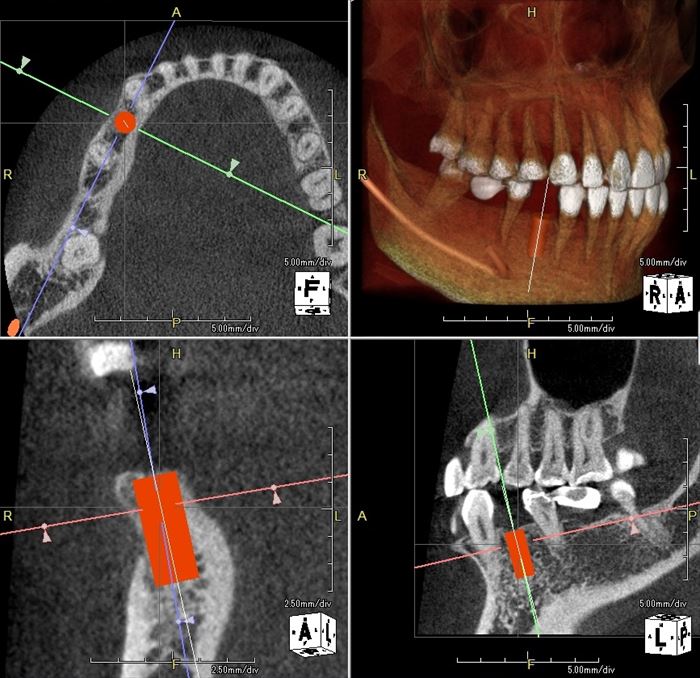

埋入位置・埋入角度をシミュレーションし、サージカルステント(ドリルガイド)を私が製作します。

サージカルステントを利用してドリリングし、深度ゲージを挿入しました。

犬歯と第一小臼歯は歯列弓の中で前歯と臼歯の移り変わる部位のため、

埋入角度のバランスを取るのが難しい位置と言えます。

デンタルレントゲン写真を撮って確認します。

わずかに近心傾斜させてドリルステップを進めます。